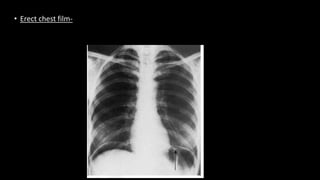

• Erect chest film-

Erect Chest Supine abdomen Erect abdomen Left lateral decubitus

Demonstrates-

-Small pneumoperitoneum

-Chest abnormalities

-Acute abdomen complicated

by chest pathology

-Acts as a baseline